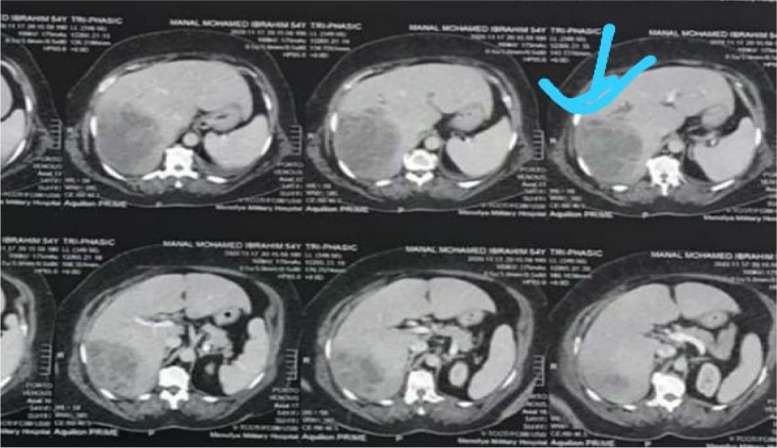

Also, immediate point of care ultrasound (POCUS) revealed a right hepatic lobe focal lesion measuring (10×10cm), along with an evident stent inside the common bile duct (CBD) (Fig. 1). A consecutive computerized tomography scan of the abdomen confirmed the right lobe focal lesion as a complex abscess occupying large area (Figs. 2 and 3).